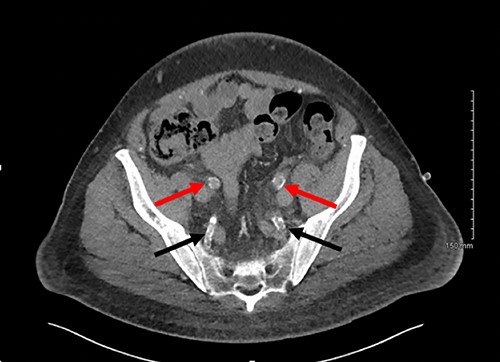

Axial slice of a non-contrast CT AP with red arrows showing calcified external iliac arteries and black arrows showing calcified internal iliac arteries.

Post-operatively the patient was experiencing ongoing severe penile, examination of the glans was not possible due to oedema and pain. Our patient underwent dialysis to offload excess fluid. A CT angiogram revealed extensive peripheral vascular arterial calcification, including calcification of the internal pudendal and cavernosal arteries (Figs 2 and 3). The inguinal lymphadenopathy was shown to be reactive.